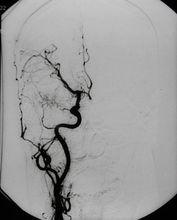

2.心血管造影 先天性肺氣腫可見異常血管或心臟畸形放射性核素肺掃描可見患葉血液灌注減少,支氣管鏡及支氣管造影用以除外其他病變。肺動脈造影:患側肺動脈細小外周血管稀少。放射性核素檢查:患肺灌注顯著減少。

1.放射學檢查 先天性肺氣腫可見病變上葉多見,以左側為主下葉極少見特徵為單葉肺透亮度增加、血管紋理減少患葉體積明顯增大、鄰近健肺受壓、不張,縱隔健側移位膈肌下移或正常,透視可見縱隔吸氣時移向患側,呼氣向健側移位。偶爾也可見到患肺密度增加,而不是高透亮度,這是因為繼發於支氣管梗阻的液體排空障礙,但其他放射學所見的特徵仍存在,液體可在24h到2周內清除此後放射學特徵(高透亮度)恢復。特異性肺氣腫X線表現為患肺透亮度增加、肺門血管紋理減少。支氣管造影:支氣管近端充盈,遠端細小5~6級以下支氣管不充盈透視見:吸氣時縱隔患側移位,患側膈肌活動度減弱,患肺容積不隨呼吸運動而改變